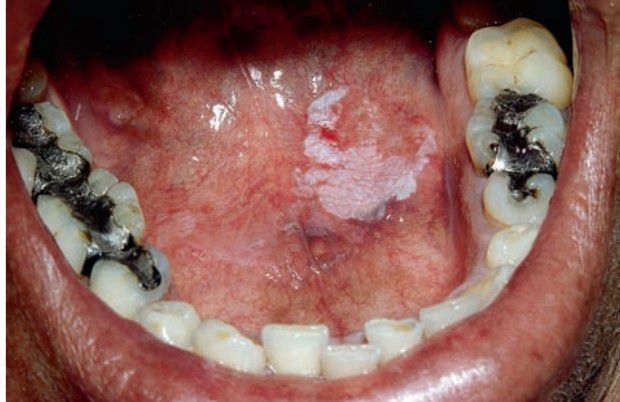

Idiopathic leukoplakia

Asymptomatic white patch; cannot be wiped off.

Leukoplakia

Idiopathic